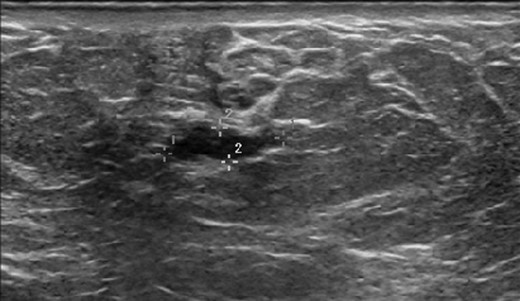

Bilateral mammogram demonstrated mild gynecomastia in both sides with no discrete mass or clusters of microcalcifications (Fig. 1). A follow-up ultrasound around the area of palpable concern did show a prominent duct with irregular contours at the 6:00 position in the left breast (Fig. 2). Excisional biopsy was recommended and a subareolar biopsy of the left breast was performed.

Diagnostic mammogram of the left (a) and right (b) breast demonstrates mild bilateral gynecomastia without discrete mass.